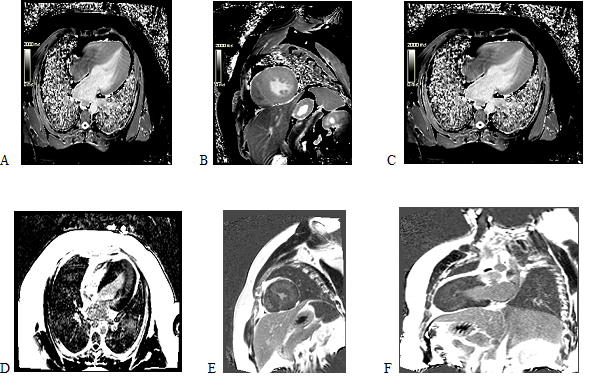

Ümumi kardiologiya

HİPERTROFİK KARDİOMİOPATİYADA (HKMP) ÜRƏK MAQNİT-REZONANS TOMOQRAFİYASININ ROLU: DİAQNOSTİKA, RİSK STRATİFİKASİYASI VƏ KLİNİK QƏRARVERMƏ Anaxanım Səfərova, Şəfa Şahbazova, Lalə Quluzadə, Leyla Musayeva, Aytən Nəsibova